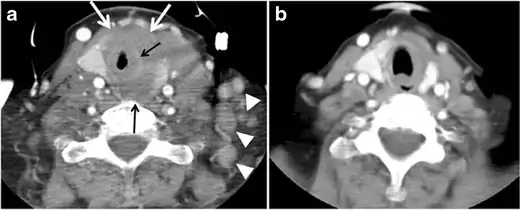

Fig. 6. A 61-year-old female patient with locally aggressive PTC. an Enhanced axial CT scan of the neck demonstrates a heterogeneous infiltrative thyroid mass. This mass diffusely involves the entire gland and circumferentially encases the trachea with involvement of bilateral tracheoesophageal grooves (white arrows). b, c Additional axial cranial images show right cricoid cartilage destruction (black arrows in b), right thyroid cartilage destruction (black arrow in c), right vocal cord paralysis (white arrows in b), and bilateral cervical lymphadenopathy (arrowheads).[1]

The radiologist must evaluate the central structures draping the thyroid gland including the trachea, oesophagus, larynx, and pharynx, as well as the recurrent laryngeal nerve. Invasion is suspected if the thyroid mass abuts the airway or oesophagus for more than 180 degrees. Luminal deformity, mucosal thickening and mucosal focal irregularity are more specific indicators of invasion. Obliteration of the fat planes of the tracheoesophageal groove in three axial images and signs of vocal cord paralysis are indicative of recurrent laryngeal nerve invasion. Invasion of these central structures meets the criteria for T4a disease (Figs. 5 and and6)6).[1]

Arterial invasion constitutes T4b disease, which may preclude curative surgery. More than 180 degrees of arterial encasement is suggestive of invasion, however, arterial deformity or narrowing is much more suspicious for invasion. The carotid artery is the most commonly involved artery; however, the mediastinal vessels should also be examined. Encasement of the carotid artery or mediastinal vessels for more than 270 degrees is unlikely to be resectable. On the other hand, occlusion or effacement of the internal jugular vein can occur without invasion and does not influence surgical resectability or staging. Asymmetry of the strap muscle and the tumour abutting its external surface are signs of an invasion. However, invasion of the pre-vertebral musculature is more challenging, as a large lesion can compress the muscle without invasion (Figs. 5 and and6)6).[1]